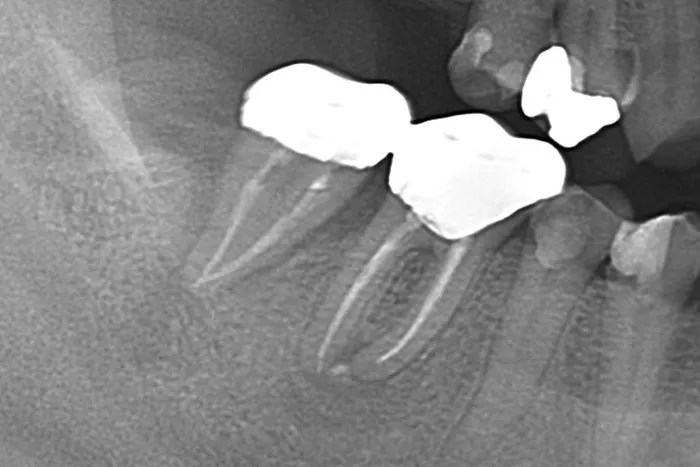

症例② 左上の歯をぶつけて他院で治療してもらったが膿みが治らない

Before

After

| 主訴 | 左上の歯をぶつけて他院で治療してもらったが膿みが治らない |

|---|---|

| 治療期間 | 4ヶ月 |

| 治療費 | 国民健康保険の範囲内 |

| 治療内容 | 根管治療・歯根端切除術・逆根幹充填(外科処置) |

| 治療のリスク | 根管治療中の炎症による痛み/外科処置後の腫れ・痛み |

▲治療のコメント

今回のケースでは、当院で再度根管治療を行いました。根尖の病変が大きく、再発を繰り返していたことより、嚢胞形成をしている可能性が高いと判断しました。そのことより、外科的な治療が必要になる可能性をお伝えした上で、経過観察を行っていました。3ヶ月後再発・排膿したので、予定通り歯根端切除と逆根幹充填を行いました。それからは再発することなく、1年経過のレントガン写真でも根尖病変の消失が確認できます。